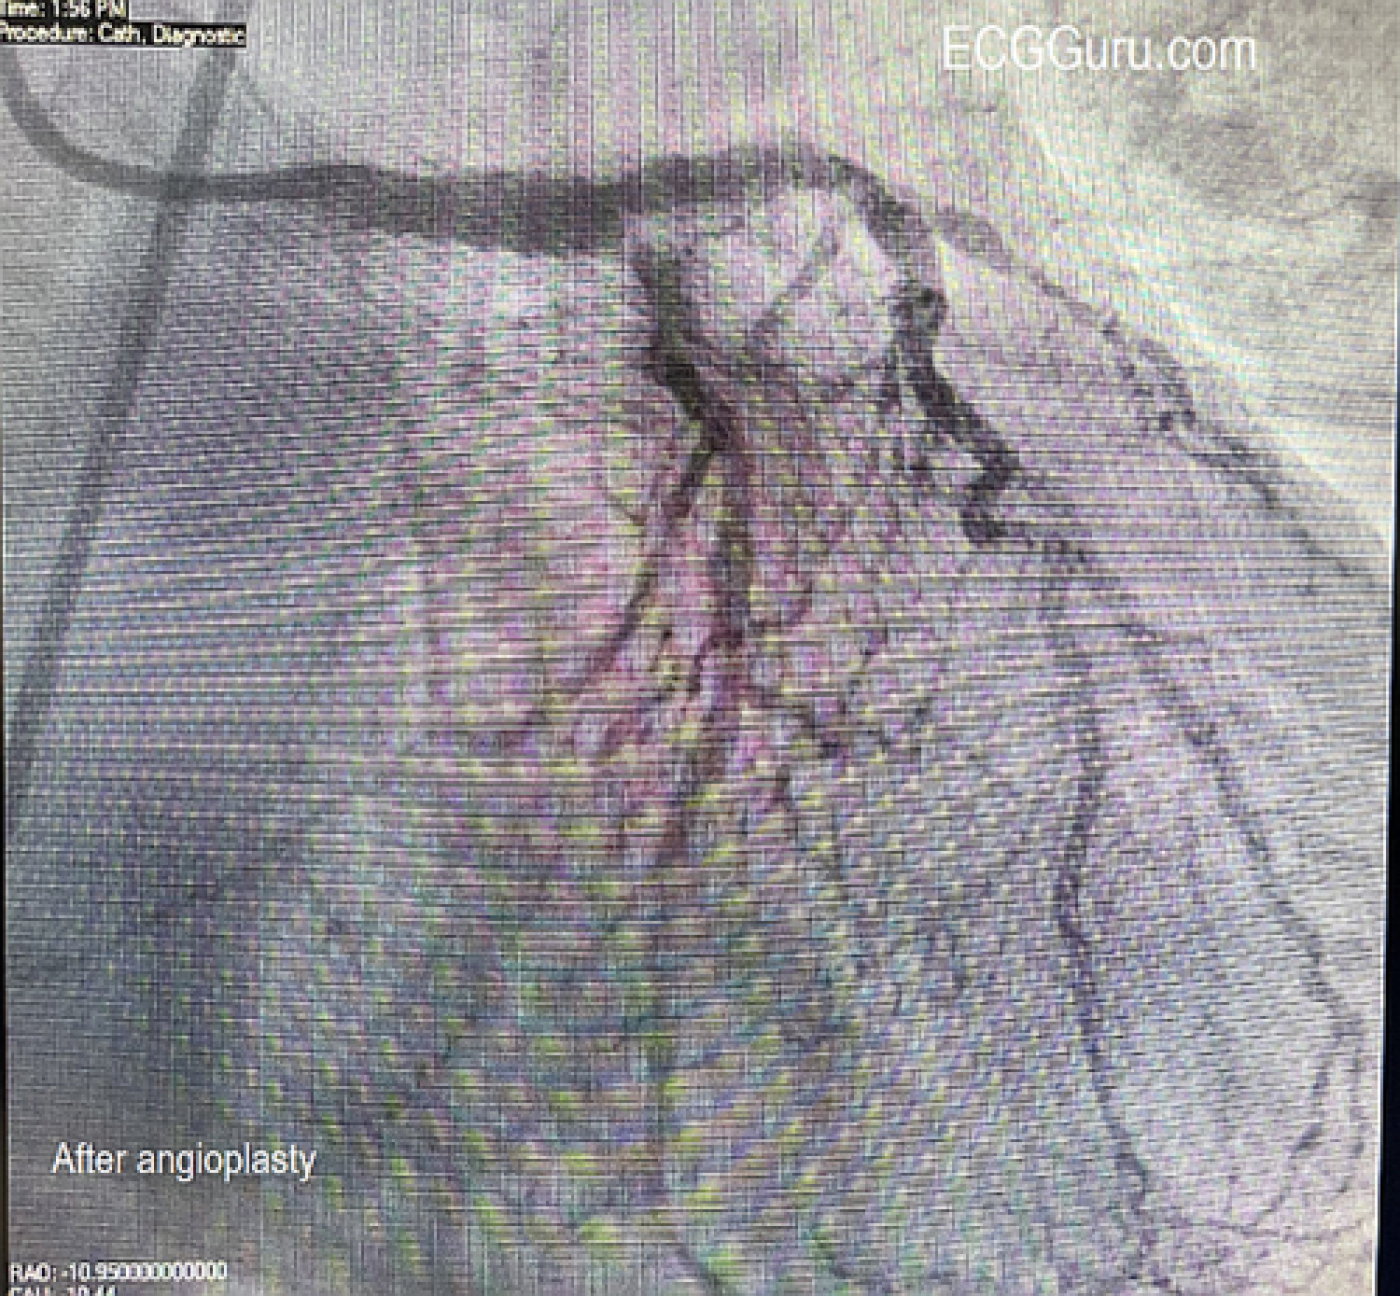

The Cath Lab: In the cath lab, the circumflex artery was found to be totally occluded. When a wire was introduced, circulation opened up, revealing an extensive collateral system from the circumflex to the area usually supplied by the RCA (inferior/posterior wall). The right coronary artery (RCA) was found to have chronic total occlusion (CTO), confirmed by the presence of the collateral system from the circumflex. The arteries show extensive disease. The patient was stabilized with an Impella (mini ventricular pump) placed due to cardiogenic shock. The ECG shows how extensive the damage can be when coronary circulation is relying on one coronary artery system (the left) to supply the entire heart. In this case, the LCx was responsible for the inferior, posterior, and lateral walls, and was occluded. The left anterior descending (LAD) artery was diseased but still patent.